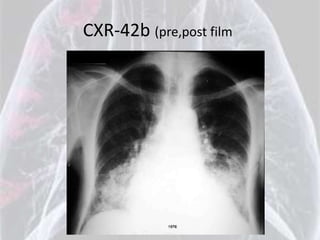

CXR-42b (pre,post film

Lipoid Pneumonia

•   Alveolar

•   Mass like densities

•   Chronic

•   Lower lung fields

•   Bilateral in this case

•   Air space density projecting over RML and

lingula

Sunday, January 06, 2013